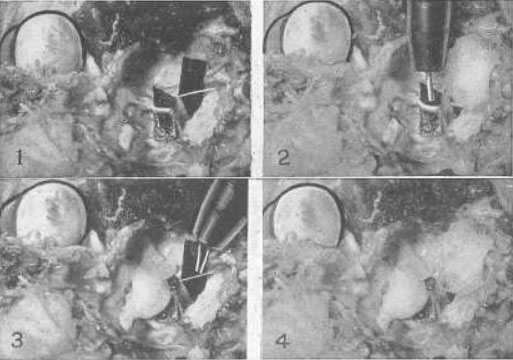

Рис. 22. Эксперимент на примере глаза кошки, демонстрирующий то, что четвертый нерв, который снабжает только верхнюю косую мышцу, является точно таким же нервом аккомодации, как и третий, и что верхняя косая мышца, которую он снабжает, есть мышца аккомодации

1 Оба нерва были выведены наружу возле их основания в головном мозге, и полоска черной бумаги была вложена позади каждого, для того чтобы изображение можно было увидеть. Четвертый нерв это тот, что поменьше. Верхняя косая мышца была перемещена путем подгибания. Так как эта мышца всегда недоразвита у кошек, то до тех пор, пока ее натяжение не усиливают, аккомодация у этих животных не воспроизводится. Стимуляция одного или обоих нервов импульсным током способствовала возникновению аккомодации.

2 Когда четвертый нерв был покрыт ватой, пропитанной нормальным физиологическим раствором, применение импульсного тока вызвало аккомодацию. Когда вата была пропитана однопроцентным раствором атропина сульфата в нормальном физиологическом растворе, не удавалось воспроизвести аккомодацию, но стимуляция третьего нерва воспроизводила ее.

3 Когда третий нерв был покрыт ватой, пропитанной нормальным физиологическим раствором, воздействием импульсного тока была воспроизведена аккомодация. Когда вата была смочена атропина сульфатом в нормальном физиологическом растворе, то не удавалось воспроизвести аккомодацию, но стимуляция четвертого нерва аккомодацию все же вызывала.

4 Когда оба нерва были покрыты ватой, пропитанной атропина сульфатом в нормальном физиологическом растворе, применение электричества к вате не вызывало возникновения аккомодации. Когда органы были вымыты в теплом физиологическом растворе, стимуляция электрическим током каждого нерва всегда воспроизводила аккомодацию. Нервы попеременно покрывались ватой, смоченной атропином, а затем промывались теплым физиологическим раствором за один час до применения электрического тока в каждом из состояний с теми же результатами. Аккомодация никогда не могла быть воспроизведена при помощи стимуляции электрическим током, когда нервы были парализованы атропином, но всегда происходила при стимуляции каждого или обоих нервов, когда их промывали физиологическим раствором. Эксперимент был проведен с теми же результатами, что и с множеством кроликов и собаками.